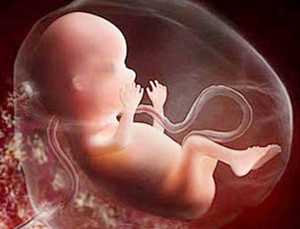

Пока у мамы состояние приходит в норму и она решает вопрос в выбором одежды, плод на 18 неделе беременности приступает к активному развитию. Таким образом, на 18 неделе беременности ребенок имеет ноги, руки и даже фаланги пальцев. Кроме того, на 18 неделе развития беременности у малыша на пальчиках образуется узор, называющийся отпечатком пальца, присущий только ребенку. Окончательно сформированы и половые органы.

В это же время осуществляется развитие мозга. Укрепляется иммунитет, ребенок на 18 неделе беременности умеет уже самостоятельно бороться с вирусами.

На 18 неделе беременности уже заканчивает формирование коренных зубцов, они находятся намного дальше, чем молочные зубы. Малыш еще не открыл глаза в этот период, но уже имеет реакцию на свет, попадающий на живот матери. Совершенствуется слух, а это говорит о том, что отныне стоит избегать чрезмерных шумов и слишком резких звуков. С этой недели будущая мать уже может напевать колыбельные, слушать классику и даже разговаривать со своим ребеночком ласково, он однозначно ее слышит.

Малыш на 18 неделе беременности имеет рост в 13-16 см, а вес — почти 200 грамм. Однако, для того, чтобы перемещаться, места в животе ему предостаточно, чем он и пользуется: прыгает, машет руками, передвигает ножками и т.д. Такие движения идут плоду на пользу, развивая работу мозга.

На 18 неделе беременности малыш развивается ускоренными темпами. Размер плода достигает 20-22 сантиметров. Вес ребенка (плода) на 18 неделе беременности составляет 160-215 граммов.

В организме у крохи происходят следующие физиологические изменения:

- Окончательно формируются ноги и руки, на крошечных пальчиках можно различить неповторимые дактилоскопические узоры.

- Начинает накапливаться слой подкожной жировой клетчатки.

- Активно развивается иммунная система: в организме плода уже выделяются иммуноглобулин и интерферон.

- Несмотря на то, что глазки малыша закрыты, сквозь тонкие веки он начинает ощущать свет и темноту, иногда даже рефлекторно моргает.

- На 18 неделе беременности ребенок активно глотает околоплодные воды, которые, пройдя через почки, выйдут в виде первой мочи сразу после рождения. Проходя через пищевой тракт, жидкость стимулирует развитие пищеварительной системы.

Ребенок активно двигает руками и ногами, правда, почувствовать это могут далеко не все. Однако если вы ощутили шевеления на 18 неделе беременности, начинайте следить за их частотой. В норме малыш должен подавать сигналы до 8 раз в течение часа. Если это происходит слишком редко или, напротив, ребенок чересчур активен, следует обратиться к врачу чтобы убедиться, что все нормально.

Ученые доказали, что на 18 неделе внутриутробного развития ребенок слышит звуки и позитивно реагирует на голоса своих родителей. Вы можете общаться с малышом, петь ему песенки или рассказывать сказки. Кстати, на 18 неделе беременности плод отлично реагирует на классическую музыку, поэтому прививать хороший вкус малышу вы можете уже сейчас.

- У него уже сформированы фаланги пальчиков на ногах и руках, появились узоры отпечатков. Черты лица становятся все более четкими.

- К 18 неделе беременности ваш ребенок может слышать и слушать звуки, поэтому можно начинать разговаривать с ним, петь ему на ночь песни и просто рассказывать что-либо. Подобное общение очень полезно и важно для ребеночка, поскольку он начинает привыкать к маминому голосу и успокаиваться, когда слышит его. Если кроха испугается и дернется, то девушка почувствует это, но добрая мелодичная песня успокоит малыша.

- Плод весит около 200 г, а его рост примерно 15 сантиметров. Половые органы уже практически сформировались.

- На 18 неделе беременности начинают укрепляться кости, а глаза плода приобретают чувствительность. Они по-прежнему практически постоянно закрыты, однако могут реагировать на свет. Продолжает укрепляться эндокринная мышечная система, благодаря чему кроха может сильнее толкать маточные стенки, чтобы поздороваться с мамочкой. Поэтому на 18 неделе беременности мамочка уже чувствует, когда малыш пинается по животу.

- Укрепляются также суставы, костная ткань. Полностью сформированы зачатки коренных зубов, а десны уже готовы к образованию молочных зубов.